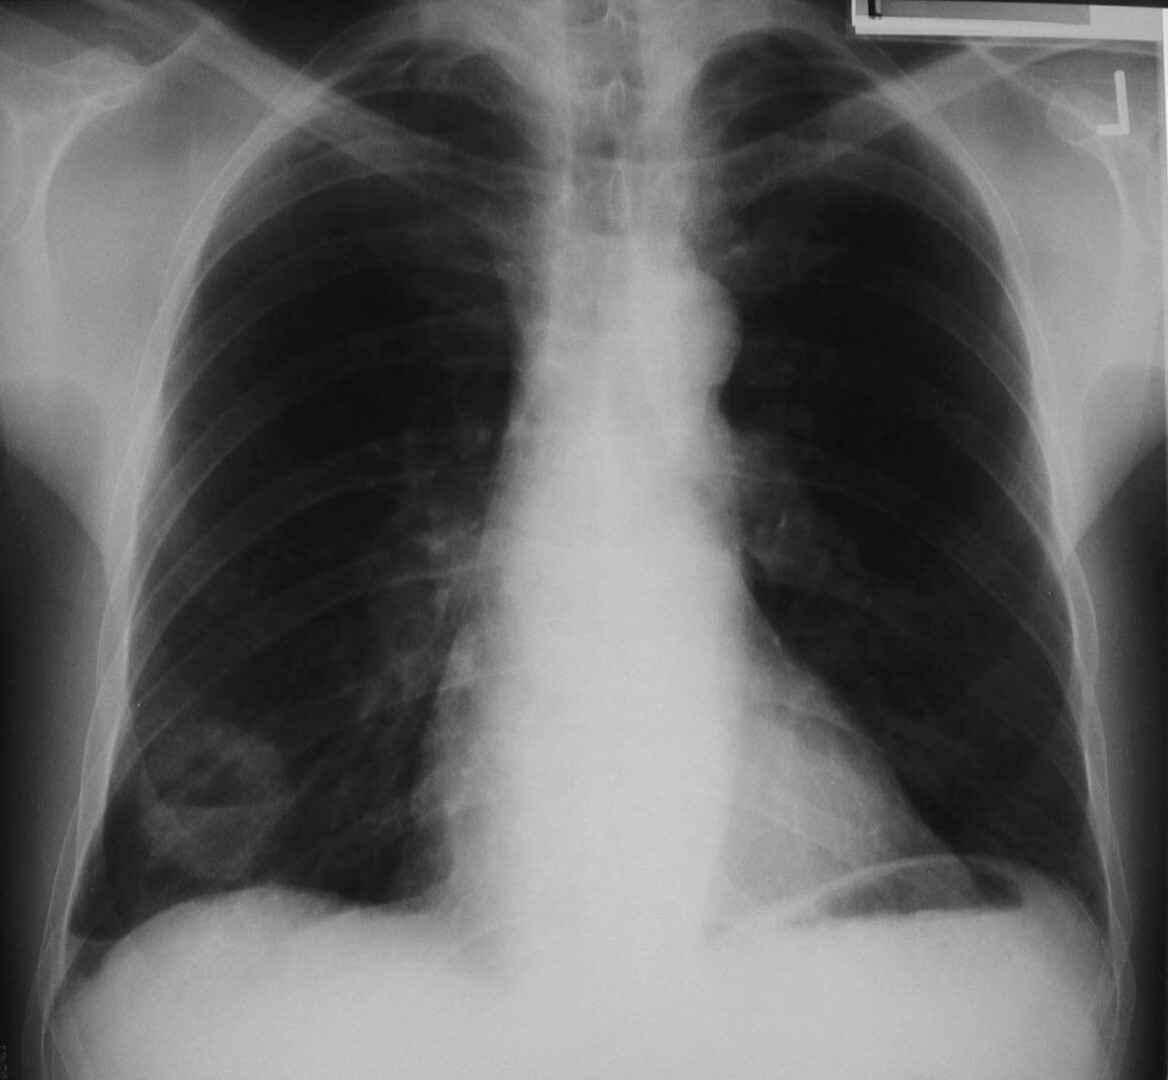

Q

x ray

A

-is this a nodule or a nipple shadow

-right lower